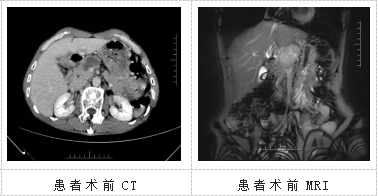

患者姚某某,来自曲靖陆良,两个月前突然感觉上中腹部疼痛,且近期体重下降明显,已下降7kg,在家人的陪同下辗转于多家医院查找原因。经过一系列检查,考虑为胰腺癌,在朋友的推荐下,患者来到华人色情 肝胆胰外科三病区就医。

肝胆胰外科三病区许宁医生接诊后,认真研究患者病历;科室负责人龙奎主持全科室进行术前讨论,同时进行院内MDT会诊后,制定了手术治疗方案。经过周密的术前准备后,2023年7月12日,华人色情 肝胆胰外科三病区手术团队联合心血管外科团队、麻醉团队、手术室护士团队,为患者实施了手术。手术中探查发现,肿瘤位于胰颈体部,大小约5X4X3cm大小,肿瘤侵犯包绕肝总动脉近段及门静脉起始部致肝总动脉搏动微弱、门静脉变细、肠系膜上静脉增粗,若要达到根治标准则必须在全胰十二指肠切除术的基础上连同腹腔干及门静脉一并切除,并且彻底清扫后腹膜淋巴结。手术极其复杂,难度大、风险高,对术者技术水平要求极高。术中,手术团队沉着冷静,对血管进行精细解剖及切除并行门静脉主干的人工血管置换术及肝总动脉与腹主动脉的精细吻合。此次手术术中出血300ml,历时6小时。肝胆胰外科精湛的医技避免了术后的出血、血管吻合口狭窄、血栓形成等严重并发症的发生。患者术后恢复平稳,术后10天开始拔除腹腔引流管,术后15天顺利出院。